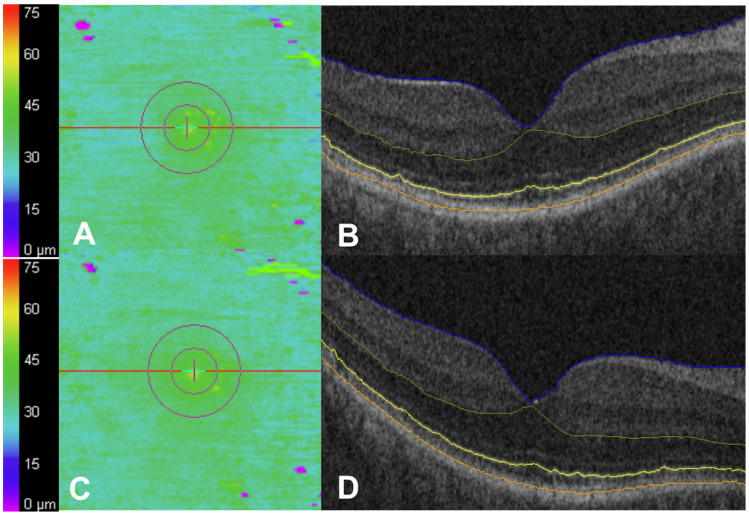

背景/目的:羟基氯喹(HCQ)视网膜病变可能在早期被忽视,因为OCT的结构改变可能先于症状出现,而且往往很微妙。早期发现对于防止不可逆转的损害至关重要。本研究利用椭球区(EZ)作图评估HCQ明显中毒前的纵向OCT变化。方法:长期HCQ患者至少间隔一年使用Cirrus HD-OCT进行两次黄斑立方体扫描。扫描结果用EZ-mapping平台进行分析,并进行人工验证。有基线OCT毒性体征或同时存在黄斑疾病的患者根据隐蔽性专家评价被排除。结果:纳入373例患者373只眼。平均年龄57.0±12.6岁,平均HCQ剂量379.4±59.4 mg,治疗时间5.6±3.7年,OCT间隔3.1±0.9年。视网膜外指标在整个队列中保持稳定。平均表面EZ衰减从3.3%增加到3.9% (p = 0.24)。34只眼(9.1%)EZ衰减绝对增加≥4% (~1.5 mm2)。这种增加与HCQ开始时的年龄(p < 0.001)、第一次和第二次OCT时的年龄(p < 0.001)、基线视力(p = 0.01)以及其他视网膜外指标的变化(p < 0.01)显著相关。在第二次10月时,只有3/34只眼(8.9%)被管理临床医生诊断为HCQ毒性。然而,经专家评审,其中26只眼(76.5%)有HCQ毒性体征,这表明与临床医生评审相比,这些定量视网膜外指标检测毒性的总体灵敏度更高。结论:纵向OCT评估显示,HCQ眼的视网膜外指标总体稳定,但有一部分EZ衰减增加,这与HCQ开始时的年龄、基线视力和专家OCT检查相关。这些变化可能有助于识别有风险的眼睛和早期毒性的眼睛,并值得进一步验证作为潜在的筛选生物标志物。

Background/Objectives: Hydroxychloroquine (HCQ) retinopathy can be underrecognized early, as structural changes in OCT may precede symptoms and are often subtle. Early detection is crucial to prevent irreversible damage. This study evaluated longitudinal OCT changes preceding overt HCQ toxicity using ellipsoid zone (EZ) mapping. Methods: Patients on long-term HCQ underwent two macular cube scans at least one year apart using Cirrus HD-OCT. Scans were analyzed with an EZ-mapping platform and manually validated. Patients with baseline OCT signs of toxicity or co-existing macular disease were excluded based on masked expert review. Results: Three hundred and seventy-three eyes of 373 patients were included. The mean age was 57.0 ± 12.6 years, the mean HCQ dose was 379.4 ± 59.4 mg, the treatment duration was 5.6 ± 3.7 years, and the OCT interval was 3.1 ± 0.9 years. Outer retinal metrics remained stable across the cohort. The mean en face EZ attenuation increased from 3.3% to 3.9% (p = 0.24). Thirty-four eyes (9.1%) experienced an absolute increase of ≥4% (~1.5 mm2) in EZ attenuation. This increase was significantly associated with age at HCQ initiation (p < 0.001), age at the time of the first and second OCT (p < 0.001), and baseline visual acuity (p = 0.01), and demonstrated changes in other outer retinal metrics (p < 0.01). Only 3/34 eyes (8.9%) were diagnosed by the managing clinician with HCQ toxicity at the time of the second OCT. However, 26 of these eyes (76.5%) had signs of HCQ toxicity by expert review, suggesting the overall greater sensitivity of these quantitative outer retinal metrics for detecting toxicity compared with clinician review. Conclusions: Longitudinal OCT assessment revealed overall stability in outer retinal metrics in eyes on HCQ, but a subset showed increased EZ attenuation, which correlated with age at the time of HCQ initiation, baseline visual acuity, and expert OCT review. These changes may help identify at-risk eyes and eyes with early toxicity and warrant further validation as potential screening biomarkers.